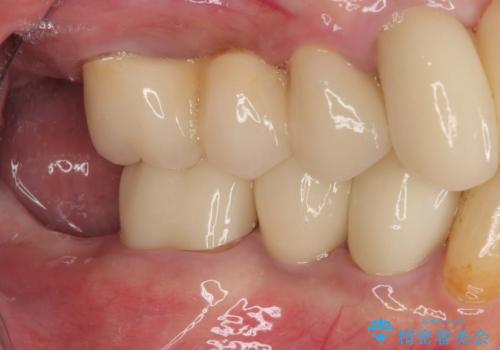

- 奥歯に装着していたクラウンが外れてしまったとのことで来院された患者様です。

診察したところ、歯根に破折線が確認され抜歯が必要な状態でした。

歯肉や歯槽骨の状態は良好であったため、抜歯即時埋入インプラントによる補綴治療を行うこととしました。

抜歯、インプラント埋入、仮歯の装着を1度に行うことができ、治療終了までわずか3か月で終えることができました。